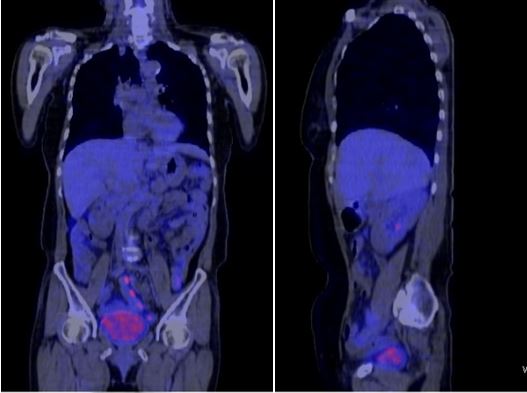

+ PET/CT :

Tại vị trí tuyến thượng thận phải có khối kích thước 3,3x3,0x4,7cm, tăng hấp thu F-18 FDG, max SUV = 15,3.

Hố chậu phải có khối kích thước 4,0x4,9x4,2cm, tăng hấp thu F-18 FDG, max SUV = 27,6.

Hình 1. Hình ảnh chụp PET/CT: Tuyến thượng thận phải có khối kích thước 3,3x3,0x4,7cm, tăng hấp thu F-18 FDG.

Hình 2. Hình ảnh chụp PET/CT: Hố chậu phải có khối kích thước 4,0x4,9x4,2cm, tăng hấp thu F-18 FDG